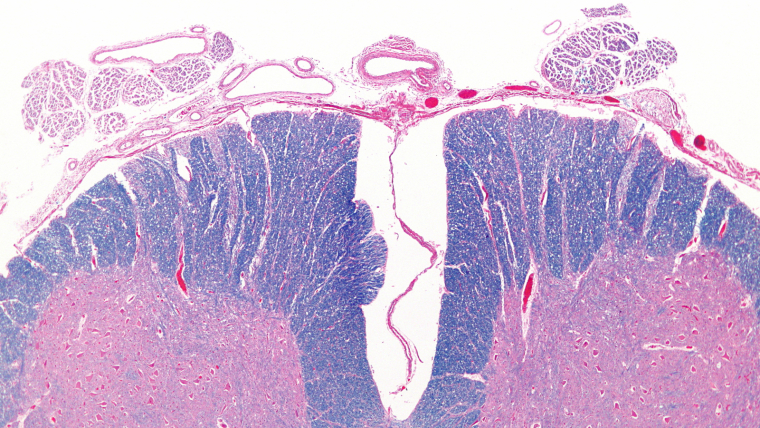

La médula espinal es un conjunto de neuronas organizadas en forma de cordón estrecho y largo situado en el interior de la columna vertebral, donde se encuentra protegida dentro del canal vertebral por las meninges al igual que el cerebro. La médula espinal cumple la función de transmitir la información entre el cerebro y el resto del cuerpo.

Esta estructura nerviosa tiene un aspecto cilíndrico y se distribuye a lo largo de la columna vertebral atravesando cada una de las 33 vértebras del cuerpo humano. Está formada por un tejido nervioso que es el resultado de la unión de neuronas, cuyos axones (la prolongación de la célula que permite la unión de unas con otras) pueden llegar a medir un metro de largo.

La médula espinal es la parte del sistema nervioso que comprende desde el agujero occipital del cráneo (foramen magnus) hasta la última de las vértebras lumbares y mide aproximadamente unos 45 centímetros en varones y 43 en mujeres.